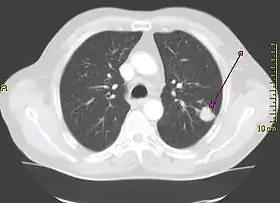

CT scan of lung, with tumor appearing as a sharp white shape

CT scan showing a cancerous tumor in the left lung

A person suspected of having lung cancer will have imaging tests done to evaluate the presence, extent, and location of tumors. First, many primary care providers perform a chest X-ray to look for a mass inside the lung.[8] The X-ray may reveal an obvious mass, the widening of the mediastinum (suggestive of spread to lymph nodes there), atelectasis (lung collapse), consolidation (pneumonia), or pleural effusion;[9] however, some lung tumors are not visible by X-ray.[5] Next, many undergo computed tomography (CT) scanning, which can reveal the sizes and locations of tumors.[8][10]